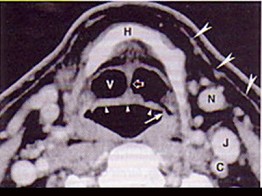

| 男,55岁,声嘶6年,有长期吸烟史。检查:无呼吸困难。喉镜检查:声带慢性充血,可见右侧声带可见菜花样新生物,右侧声带活动固定,喉部CT检查如下图: |

6.诊断首先考虑 ( )![]() ![]() ![]() ![]() |